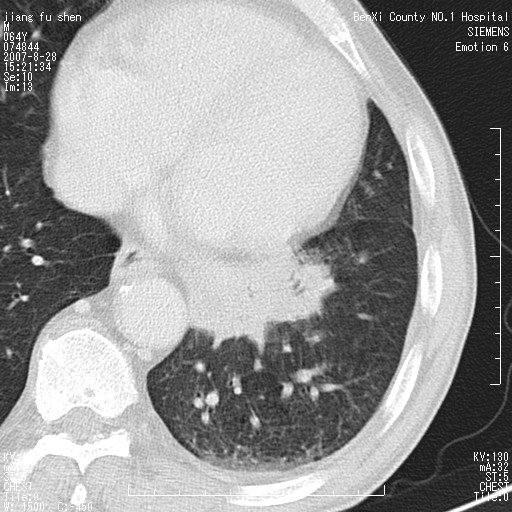

男、64、咳嗽、发烧一周、左肺呼吸音稍弱。既往肺结核,右手结核。

本次扫描患者未带原片,左肺下叶发现病灶。左肺上叶空洞,5组淋巴结肿大,1cm左右。

追问病史三月份ct扫描左肺上叶空洞,医大诊断肺结核。

平扫20-33hu

增强31-33hu

1分半44-52

2分55-67

左肺下叶前内基底段支气管明显偏心性狭窄,周围分叶状肿块,伴有阻塞性肺炎,支持肺癌可能性大。

考虑左肺中央型肺癌并阻塞性肺炎

病灶边缘可见多量较长棘影及纤维条索状影,除外病灶边缘较光整,病灶有分叶表现,但多表现为较浅分叶,且向周围伸出之叶多呈尖角改变,且边缘较光整,病灶增强呈中度延时增强,且早期及中期仅轻度增强,结合患者病史,多考虑继发型肺结核,炎性增殖灶形成,不除外肺癌

左下叶支气管变窄,管腔光滑。软组织形状不规侧,分叶呈角形。结合病史考虑结核可能性大。肺癌不除。